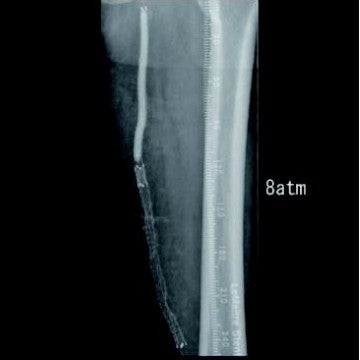

[治療] 右総大腿動脈(common femoral artery:CFA)を逆行性にエコーガイド下に穿刺。山越えで左 CFAまで6 Frガイディングシースを進めた。造影で左SFA起始部付近からベアステント遠位端のやや中枢側まで、TOSAKA分類3のISO病変があることを確認した。ところどころ病変が硬く、0.014 inchガイドワイヤーの先端2.8 gと先端12 gを順次使用して閉塞部位を突破した。PTAバルーン4 mm × 250 mmで前拡張したのち、病変部をカバーするように左SFA末梢側から左SFA起始部にかけてバイアバーン® ステントグラフト6 mm × 250 mmと6 mm × 100 mmを留置し、閉塞したベアステントをフルカバーした。バルーン5 mm × 220 mmで後拡張を実施、血管内超音波(IVUS)と造影で病変部の良好な拡張、血流を確認し手技を終了した(図3)。足関節上腕血圧比(ABI)は0.68から0.92に改善した。さらに6年が経過し、間欠性跛行の再燃があり、ステントグラフトは開存していたが(図4-1)、さらに末梢の膝窩動脈での石灰化プラークによる閉塞病変(図4-2)が原因と考えられた。アテレクトミーデバイスとDCBで膝窩動脈病変を治療して症状は消失した。run offが不良であったにもかかわらず、中枢側のステントグラフトが6年間開存していたことは特筆すべきことである。同患者については現在まで15年にわたり経過をみているが、経年的に動脈硬化が進んでおり、通常のステントやバルーンでの治療部は再治療を繰り返している。その中でステントグラフトを留置した長区間ISO病変は6年間開存を保っていたというのは、物理的に内膜過形成をシャットアウトするステントグラフトでしかみられない現象であると思われる。ISO病変に対するバイアバーン® ステントグラフトの使用が保険適用されるようになったことは、血管内治療医や患者に福音をもたらしたのではないだろうか。